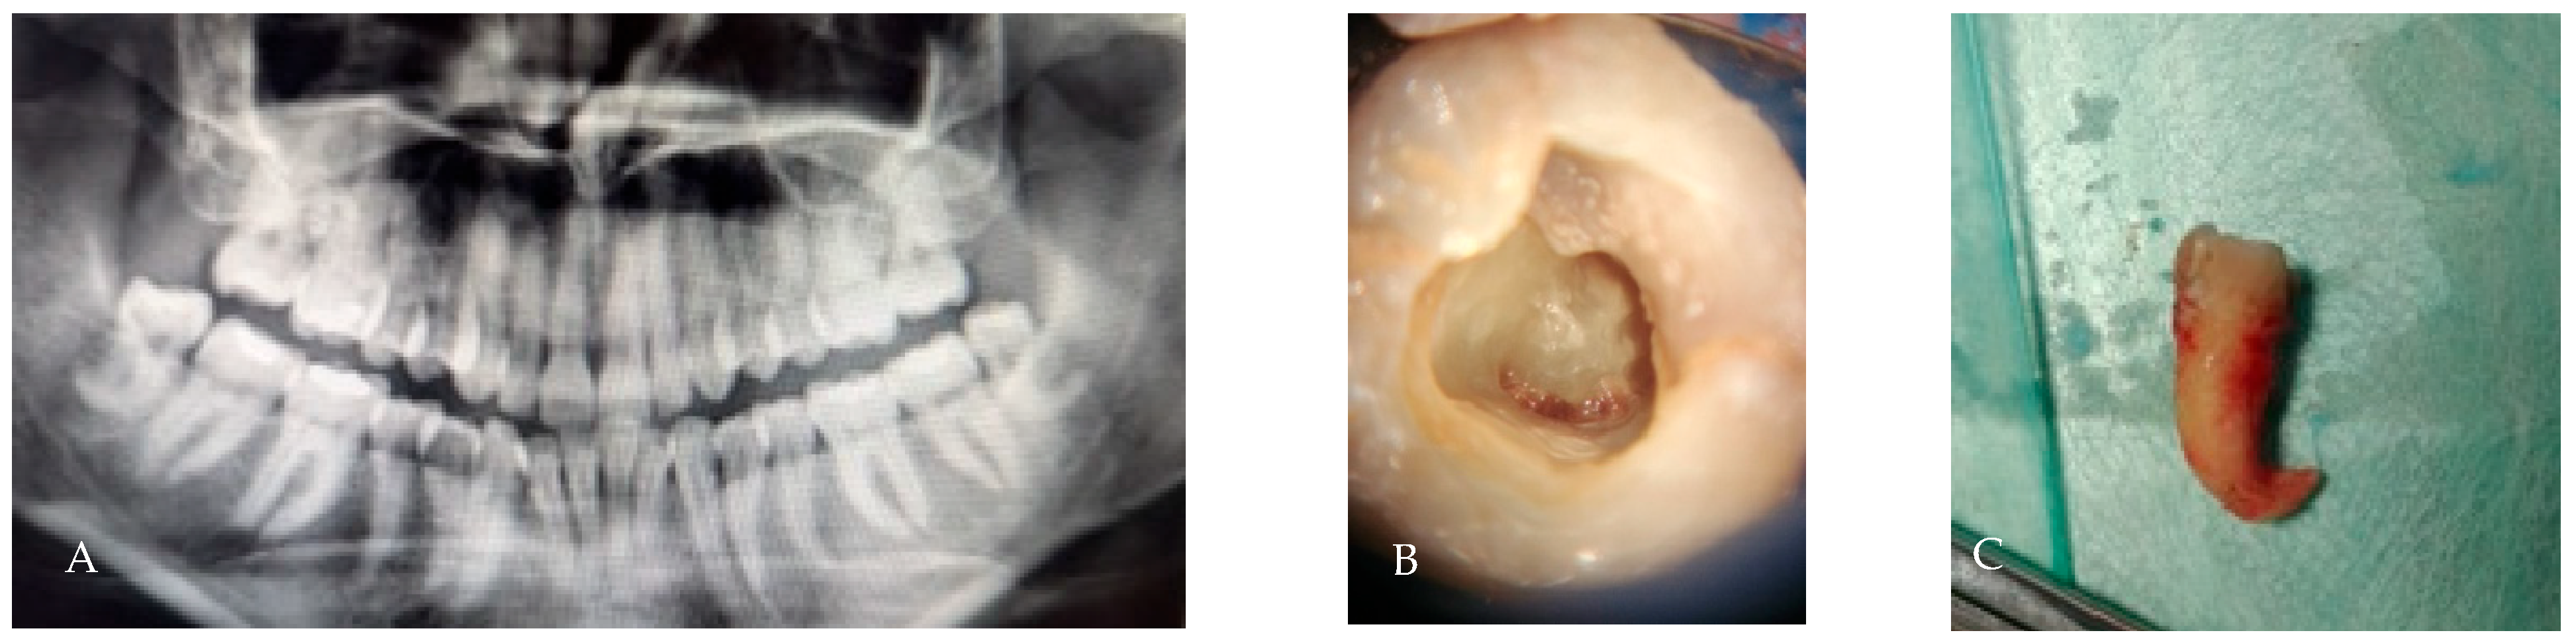

3.6. C-Shaped Morphology

- C1: continuous C-shaped canal.

- C2: semicolon-shaped (due to discontinuation of the “C”).

- C3: two or more discrete canals without a clear C-shape.

- C4: single round or oval canal.

| C-shaped canal | Fused root forming crescent or semicolon canal | 10–17% | Thin dentin walls; controlled sectioning; avoid excessive force; apex release | [7] |

| C-shaped | 10–17% | Controlled sectioning; thin dentin risk | [7,17] |